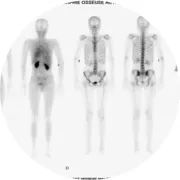

La Médecine Nucléaire se décline en une multitude d’examens d’imagerie médicale appelés « scintigraphies ». Celles-ci sont réalisées dans le but d’explorer le fonctionnement d’un organe, en injectant un vecteur (médicament dirigé vers un ou plusieurs organes) associé à un traceur très faiblement radioactif.

Le vecteur associé au traceur constituent le radiopharmaceutique qui est injecté par voie intraveineuse par les manipulateurs. L’injection n’est pas douloureuse et ces médicaments n’entraînent pas d’allergies, ni d’effets indésirables.Les rayonnements émis sont captés par des gammas-caméras et retranscrits en images, qui une fois traitées, seront interprétées par les médecins scintigraphistes.

Chaque scintigraphie est différente selon l’organe étudié et le produit radiopharmaceutique utilisé, choisi en fonction de la question posée par votre médecin.On peut étudier par exemple le cœur, les os, les poumons, la thyroïde, le cerveau, etc. Le temps d’examen est également différent selon le type de scintigraphie.